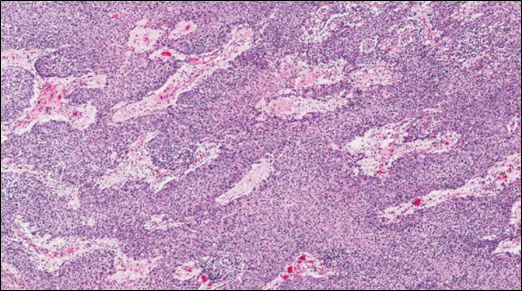

Much of the center of this mediastinal mass is effaced by extensive areas of necrosis and cystic degeneration. Sections were taken from the remaining thin peripheral rim of intact tissue that is surrounded by a variably thick, dense fibrous capsule. Neoplastic tissue is composed of highly cellular, infiltrates of plump spindloid to polygonal cells which are arranged in coalescing trabeculae and sheets and are intermingled with moderate to large numbers of small lymphocytes. These infiltrates multifocally infiltrate the surrounding capsule and are supported by small amounts of fine fibrovascular stroma which often forms dissecting thick bands and thinner septa. Frequently scattered within these infiltrates are small clusters of pale, polygonal, epithelial cells with glassy, keratinized, cytoplasm that are sometimes partially mineralized (Hassall’s corpuscles). The interstitium within the mass is also multifocally, mildly to moderately, expanded by pale poorly cellular fine fibrous stroma which often contains variably sized, deposits of basophilic, granular mineral. The majority of neoplastic polygonal to spindloid cells exhibit strong cytoplasmic staining with cytokeratin. Most of the small lymphocytes scattered within the mass were CD3 positive.The masses noted in the lung consist of similar, nodular mixed infiltrates of pale polygonal to spindloid cells intermingled with numerous small lymphocytes. These mixed infiltrates often dilated and fill pulmonary arteries and veins. Frequent scattered small deposits of mineral, foci of lytic and coagulative necrosis are also often scattered within these metastatic nodules.

Histologically, thymomas can vary greatly in appearance and in composition. Neoplastic cells are epithelial and originated from endoderm of the third pharyngeal pouch in the fetus2. Tumor cells may appear polygonal and/or spindloid, and are accompanied by variable, sometimes large, numbers of mature, non-neoplastic lymphocytes. As in this case, neoplastic cells exhibit cytoplasmic staining with cytokeratins and most of the small lymphocytes present within the tumor are small CD3+ T cells. Thymomas have been sub-categorized, based on cellular composition as lymphocyte predominant, epithelial predominate, or mixed. A variety of sub-types have also been identified (clear cell, spindle cell, pigmented)8. A clear association with prognosis and these sub-types has not been identified in veterinary medicine. In human medicine, the 2004 World Health Organization (WHO) classification scheme of thymic epithelial tumors was created to better correlate histologic findings with the clinical behavior of these tumors. This system is also based on the cell morphology of neoplastic epithelial cells and the relative proportion of non-neoplastic lymphocytes present and appears to be applicable to canine thymomas9.